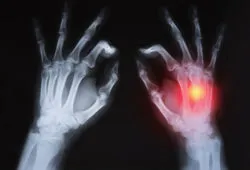

Gout is a form of arthritis that occurs when there is a build up of uric acid. This can lead to severe pain, swelling and redness in at least one joint. Allopurinol and Uloric work by lowering the uric acid levels in the blood.